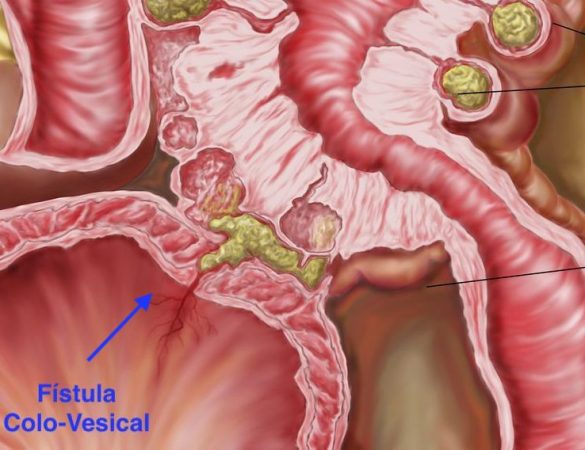

El Cáncer de Colon o Cáncer Colorrectal es un tumor maligno que aparece inicialmente en el colon o el recto y posteriormente puede invadir otras partes del cuerpo, como la vejiga, la matriz, intestinos, los pulmones, el hígado, etc. Es una enfermedad mortal si no se trata a tiempo. Tanto en México como a nivel mundial, es el tercer tipo de cáncer más frecuente en adultos. Además, el Cáncer de Colonpuede aparecer en cualquier persona ya que de cada 10 pacientes, en 9 no hay ningún antecedente de cáncer en la familia.

Al inicio, los pacientes no tienen síntomas. Después aparece sangrado al evacuar (de color rojo obscuro y mezclado dentro de la materia fecal), alteración de los hábitos usuales de la defecación (ya sea estreñimiento o diarrea, o ir mas menos frecuente al baño de lo usual, o hacer del baño un día si y un día no cuando antes iba del diario, o, por el contrario, hacer diario del baño cuando antes solo iba una vez cada tener día), evacuaciones delgadas y aplanadas o disminución de peso de forma inexplicable. El dolor es un síntoma que aparece mucho después y al principio es tan leve que no se le da importancia; sólo cuando el problema está muy avanzado el dolor ya es intenso.

Como los síntomas no siempre son muy evidentes, se necesita revisar por dentro todo el colon y el recto mediante una colonoscopía (aunque también podría hacerse un colon por enema). Si se observa alguna lesión sospechosa, se debe tomar una muestra para mandarla a analizar (biopsia). En caso de que se corrobore el cáncer, es necesario realizar varios estudios para determinar que tan avanzado está (Tomografía, Ultrasonido, Antígeno Carcino-Embrionario, etc.).

Existen diversos tratamientos que se indican de acuerdo al caso. En caso de encontrar lesiones pre-cancerosas se pueden retirar en el mismo momento de la colonoscopía o mediante cirugía. En caso de que se trate de cáncer, se realizar cirugía, radioterapia, quimioterapia, o una combinación de éstas de acuerdo al caso. Su médico le podrá indicar el tratamiento exacto después de valorarlo.